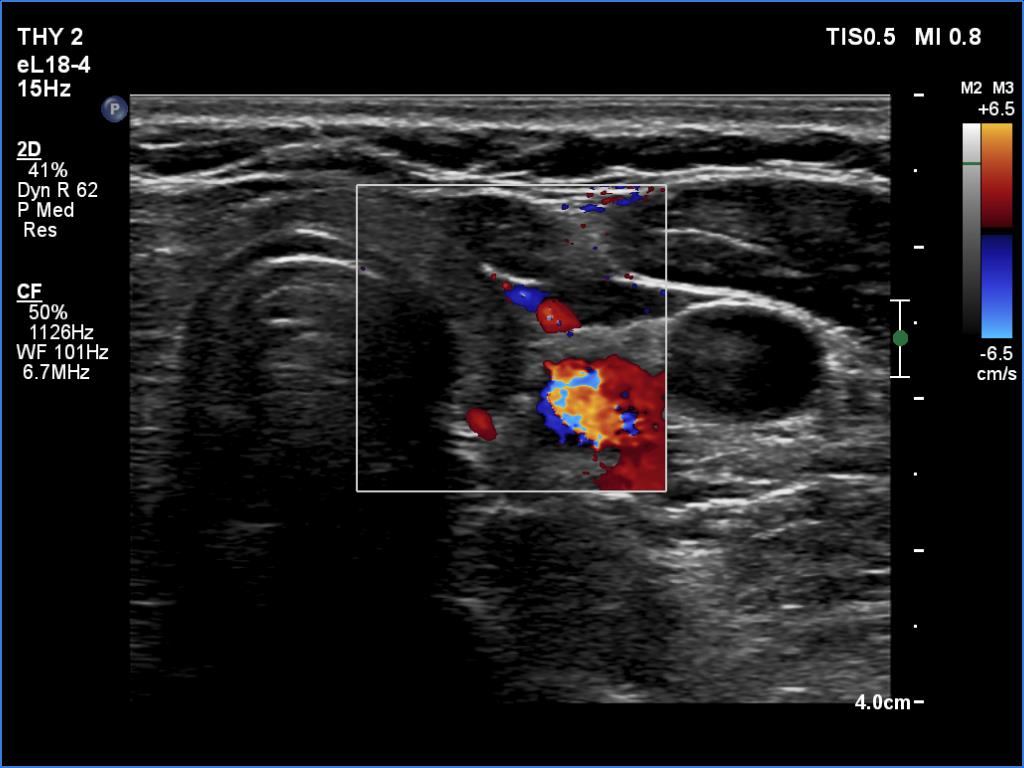

Follow-up examination five years later (ultrasonographic picture 7)

Left lobe, longitudinal scan, color Doppler mode. The vascularity is decreased.